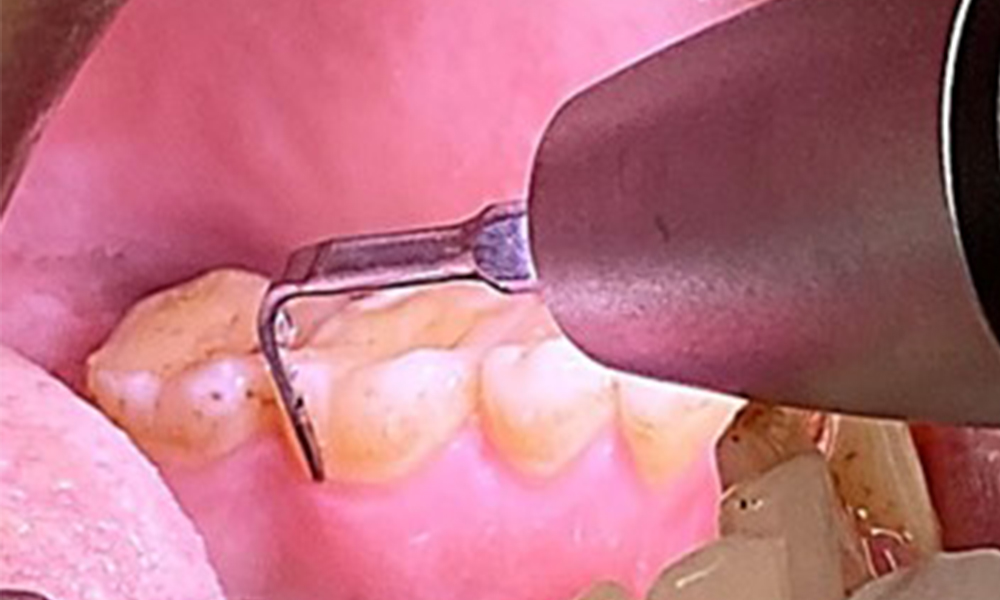

Due to the otherwise favourable general medical condition, the needs determined during the intraoral examination will be decisive for their treatment. It will be essential to periodically determine the probing depths. Gingival bleeding decreases in smokers, which is why the clinical diagnosis of periodontitis can only be made by probing (Fig. 7). Placing exclusive focus on the determination of bleeding indices may obscure existing periodontitis or gingivitis. (5)